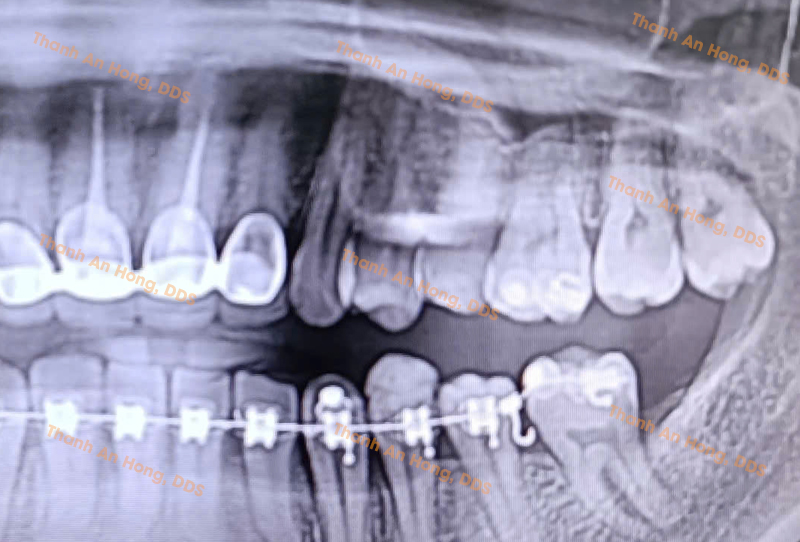

HÌNH ẢNH THỰC TẾ

Dì Gân Răng Cối Lớn Hàm Dưới